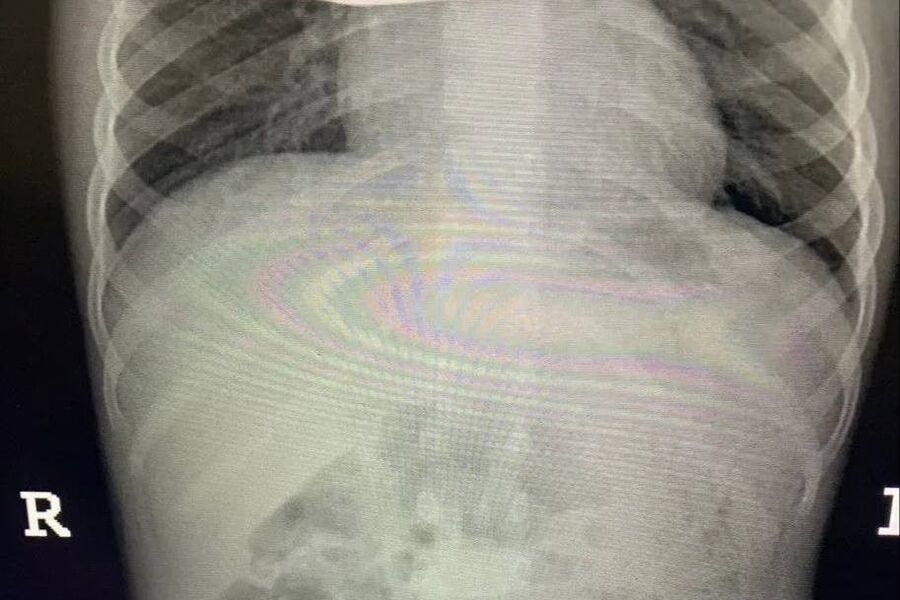

Инцидент произошел в Балашихе — малолетнюю пациентку с жалобами на острую боль в животе доставила в больницу бригада скорой помощи. Обследование показало, что внутри у ребенка большое количество металлических инородных тел. Девочку немедленно отправили на операционный стол.

Врачи приняли решение обойтись без полостного вмешательства. Через крошечные проколы специалисты аккуратно извлекли 20 магнитов из организма ребенка — они успели притянуться друг к другу и прожечь стенку кишки насквозь. Пять штук и вовсе мигрировали в область малого таза.